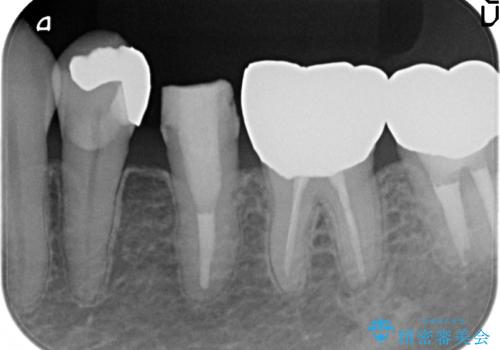

- 左下5番目の歯を根管治療からやり直したいといらっしゃった方の症例です。

再根管治療終了後、オールセラミッククラウンによる補綴を行いました。

- オールセラミッククラウン…¥100,000、仮歯…¥10,000、ファイバーコア…¥20,000費用は治療当時の料金となります